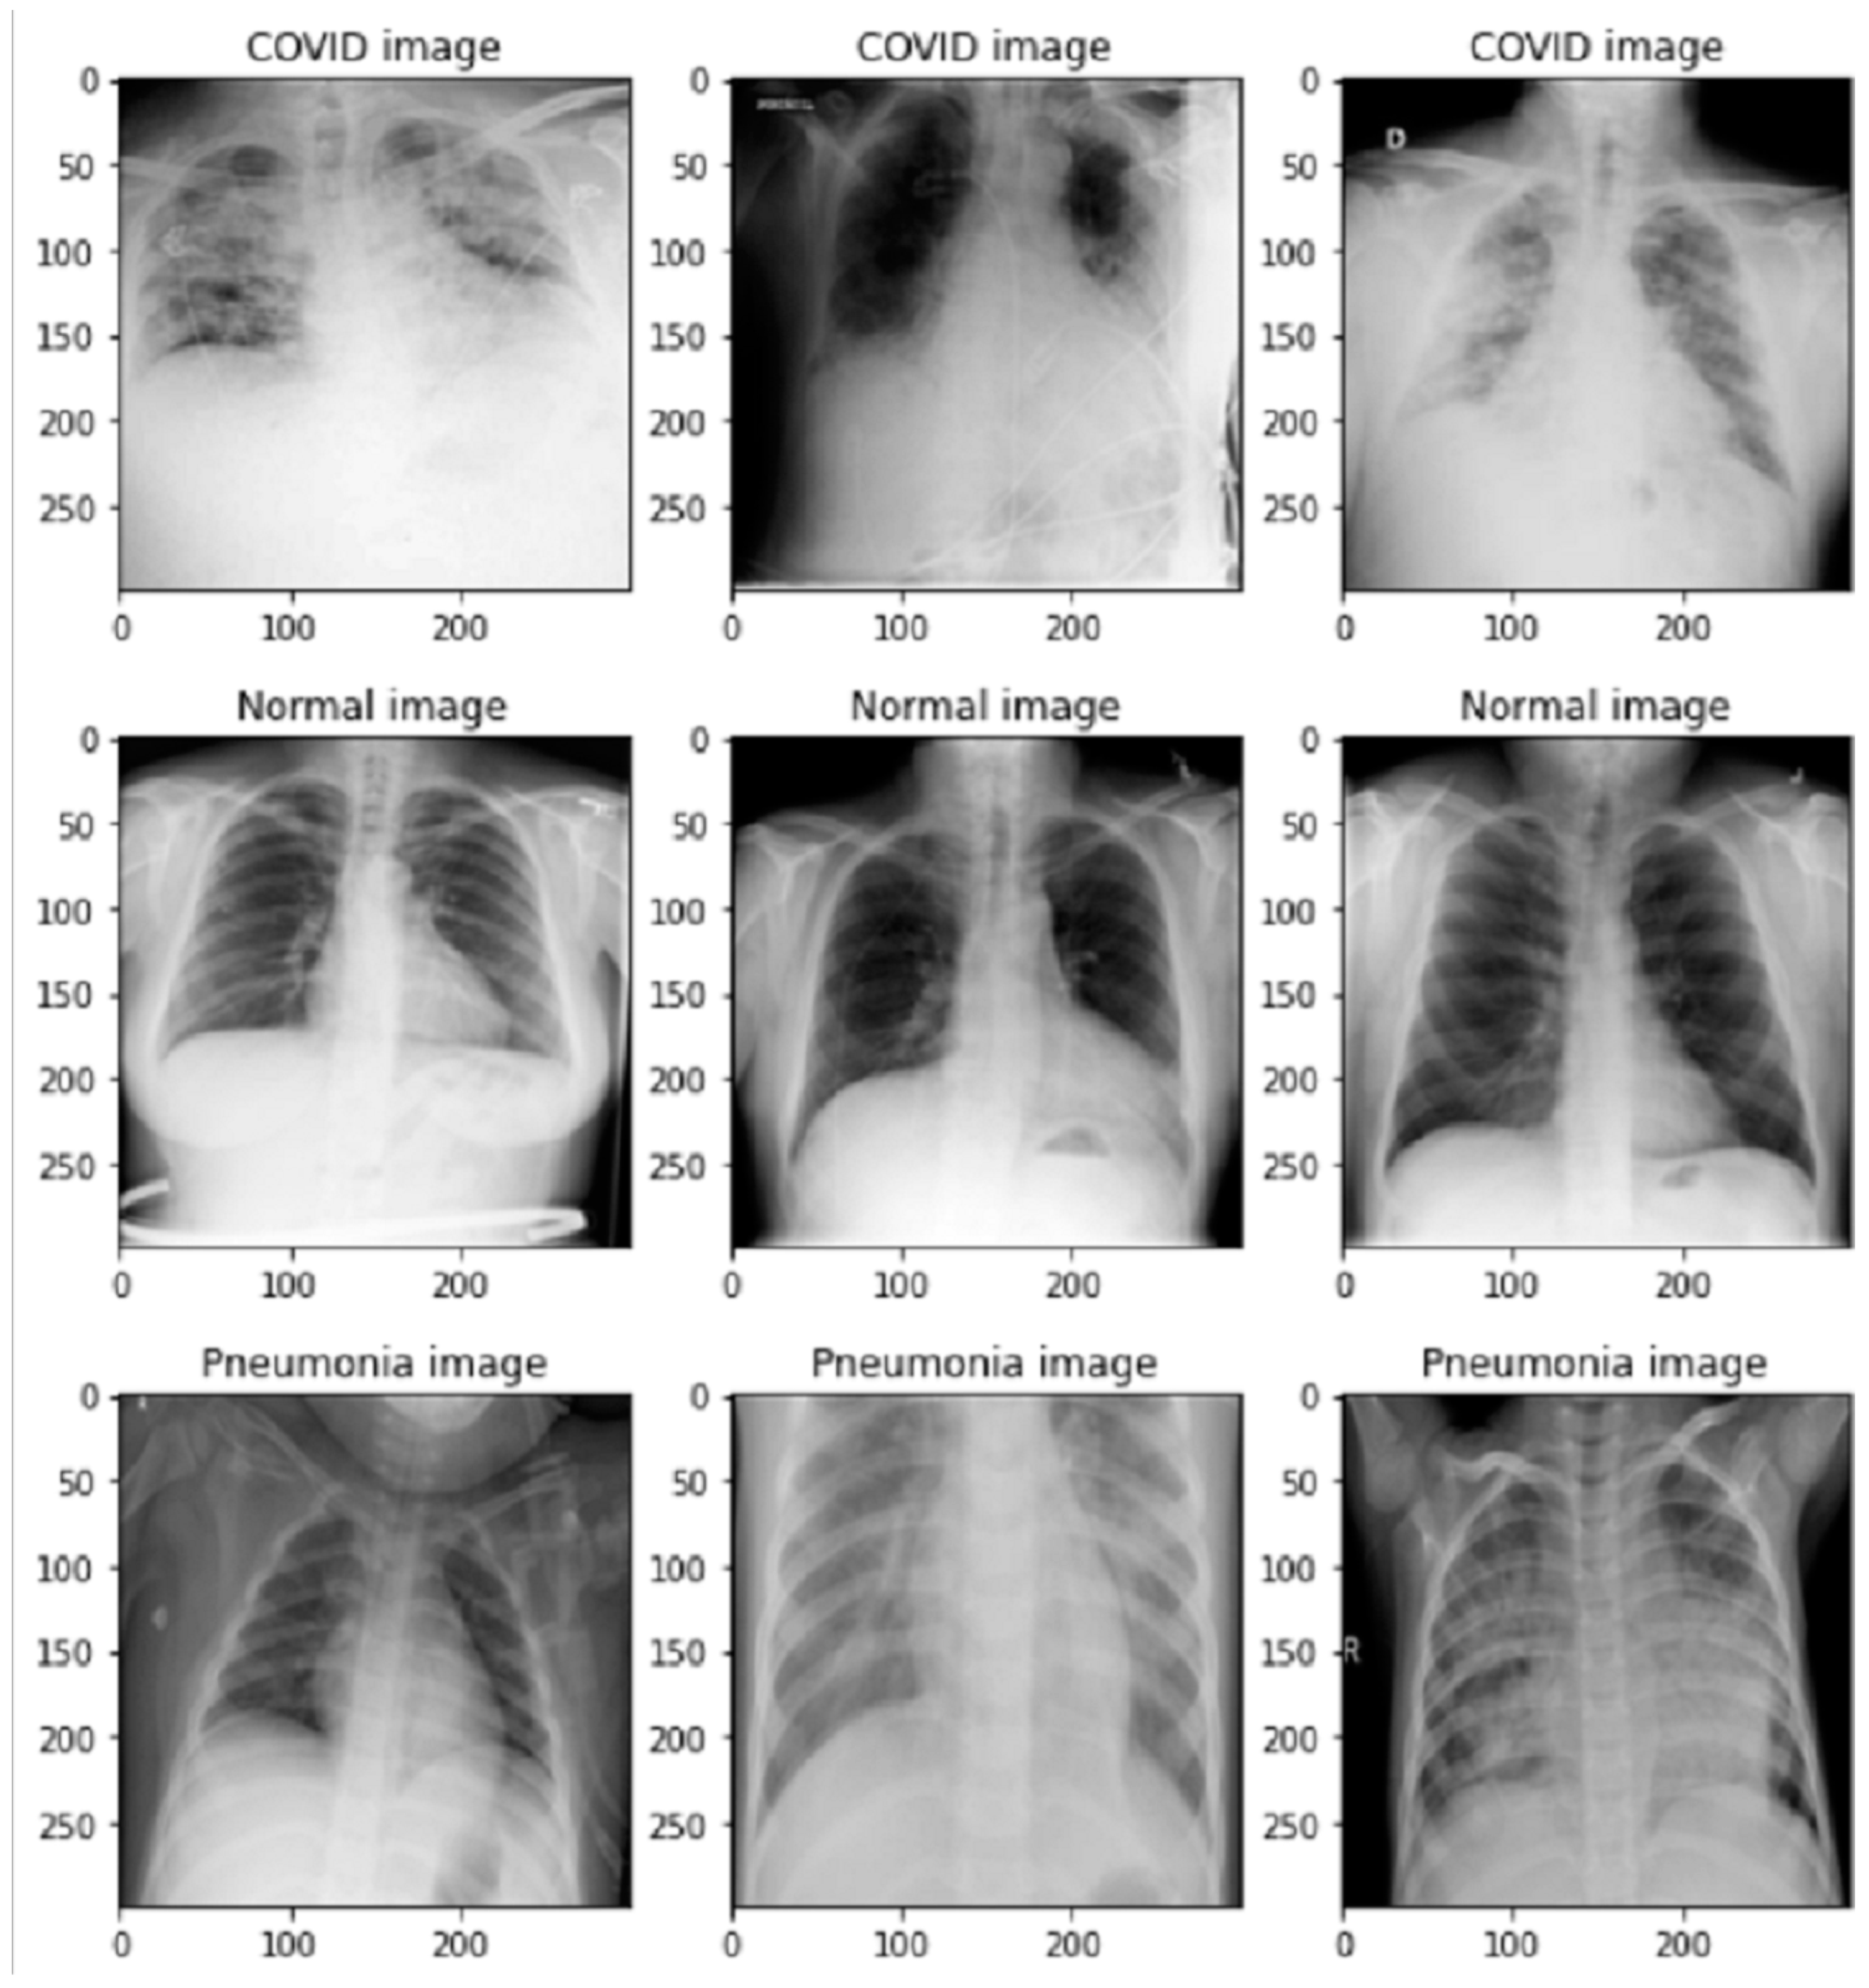

This study used a dataset from Kaggle [33,34] that contained three classes (COVID-19, normal, and pneumonia) shown in Figure 1. A total of 15,153 images (10,912 normal; 3616 COVID-19; and 1345 pneumonia) were used in this study, with 90% used for training and 10% used for validation. The proportion of splitting data can be seen in Table 1.

Figure 1.

Images of normal, COVID-19, and pneumonia.